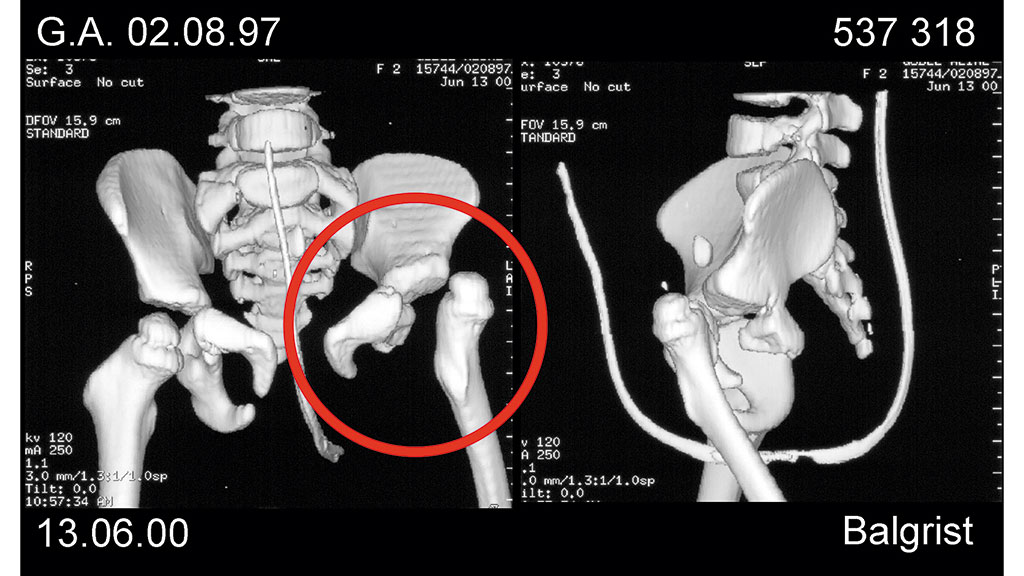

Hier handelte es sich um ein heute 16-jähriges Mädchen mit einer Dysmelie (Abb. 1) der linken unteren Extremität, deren Unterschenkel als langer, spitzer, nicht belastbarer Dorn gewachsen ist. Um einen belastungsfähigen Stumpf zu erhalten, wurde 2001 eine Knie-Exartikulation durchgeführt. Die gleichseitige Hüfte ist dysplastisch (Abb. 2) und luxiert nach ventral, hinzu kommen Stuhl- und Harninkontinenz. Nach der Knie-Exartikulation war der Stumpf nun belastungsfähig, aber nicht alleine tragfähig, da die Hüfte der Belastung nicht Stand hielt (Abb. 3).